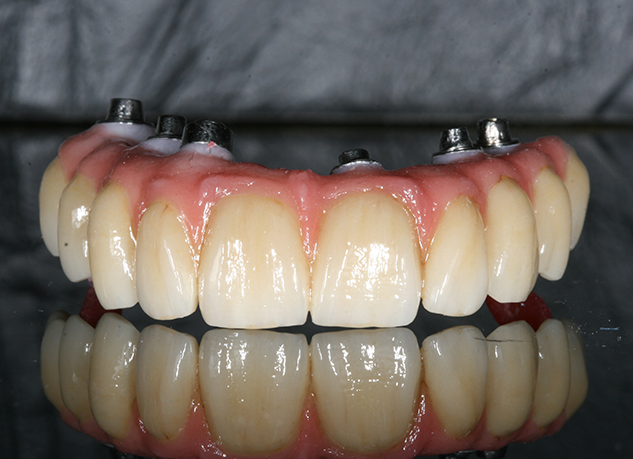

Paciente de 76 anos do sexo masculino

Motivo da consulta: Paciente desdentado total, procurava colocar dentes.

Plano de tratamento: Colocação de 4 implantes superiores e 2 implantes inferiores. Confeção de uma barra superior e colocação de 2 locators® na parte inferior. Confeção de uma prótese superior e outra inferior removível, com encaixes na barra e locators®.

A escolha deste plano de tratamento deve-se ao facto de o paciente querer uma solução total, mas não completamente fixa, uma vez que não tinha muita destreza manual para higienizar uma prótese fixa. Desta forma, conseguiu uma solução bastante retentiva (devido aos encaixes) mas que consegue remover para uma higienização correta.